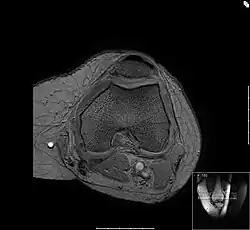

Die Bewegungsprüfung zeigt bei der Chondropathia patellae Reibegeräusche oder ein Knirschen im Gleitlager der Kniescheibe sowie häufig einen Kniescheibenanpressdruck. Der Arzt kann bei der körperlichen Untersuchung bestimmte Phänomene auslösen, die allesamt den Reizzustand des Kniescheibengleitlagers nachweisen. Reizergüsse oder Kapselschwellungen können auftreten, sind aber nicht unbedingt vorhanden. Es gibt eine spezielle Lagerung des Kniegelenkes beim Röntgen, in der das Gleitlager zwischen Kniescheibe und Oberschenkelknochen in verschiedenen Funktionszuständen dargestellt wird, die Aussagekraft ist jedoch begrenzt in Bezug auf die Knorpelschädigung. Gut beurteilt werden kann hingegen die Form des Gleitlagers, also die korrespondierenden Gelenkanteile des Femoropatellargelenkes. Eine ungünstige Kniescheibenform beispielsweise, die sogenannte Patelladysplasie führt zu einer nachteiligen Druckverteilung auf den Knorpel der Kniescheibenrückfläche und stellt somit eine Prädisposition für die Entstehung der Chondropathia patellae dar. Das MRT als weiteres bildgebendes Verfahren zeigt im Gegensatz zur Röntgendiagnostik auch krankhafte Veränderungen des Knorpels selbst.

Das Bild zeigt einen Querschnitt durch die Knochen des Oberschenkels, die Femurkondylen. Im oberen Bereich des Bildes liegt die Kniescheibe. Gut zur Darstellung kommt die Feinstruktur des Knochens, die sogenannte Spongiosa.

Zwischen Kniescheibe und dem Oberschenkel ist die Knorpelschicht zu sehen, der feine, graue Saum dazwischen ist die Gelenkflüssigkeit. Im unteren Teil des Bildes ist die Kniekehle mit den durchlaufenden Gefäßen. Die Gelenkkapsel umgibt den Oberschenkel und die Kniescheibe, man sieht angedeutet die Faserstruktur. Das wabige, hell dargestellte Material ist Körperfett.